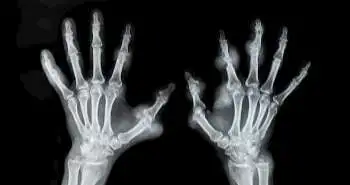

Magnetic Resonance Imaging of the hand and wrist in a study of Infliximab for rheumatoid arthritis: Comparison of dynamic contrast enhanced assessments with semi-quantitative scoring

As per the evidences MRI has been more sensitive technique than radiography for detecting joint destruction in RA patients. A method developed by OMERACT (Outcome Measures in Rheumatology) known as RAMRIS is the widely used method for monitoring bone erosion, osteitis and synovitis with MRI in RA.  The 9-point cartilage score (CARLOS) is the another most commonly used MRI method for evaluating cartilage loss in RA. Dynamic contrast-enhanced MRI (DCE-MRI) is a quantitative method for assessing synovitis. It is based on the rate and magnitude of enhancement of synovial tissue by intravenously administered gadolinium-based contrast agents (GBCAs). However, it is more difficult to perform than the conventional contrast-enhanced MRI.

The present study by Chan Beals et al. have overcome these challenges by designing a DCE-MRI technique that simultaneously imaged the entire wrist and MCP joints. They compared the short-term discriminative power and sensitivity to change of the volume transfer rate of GBCA from the blood plasma in synovium (Ktrans) with those of RAMRIS-synovitis in a randomized, controlled, multicenter trial of infliximab plus methotrexate (MTX) versus placebo plus MTX in patients with active RA. Both imaging methods similarly discriminated infliximab treatment from placebo on measures related to synovial inflammation yet remained stable during placebo treatment. The RAMRIS and CARLOS methods had additional utility of identifying damage to bone and cartilage that could be prevented by infliximab. Appropriate MRI techniques, along with clinical measures of RA activity, should improve the characterization of drug effects on inflammation and structural damage in RA.

To compare the scope and the discriminative power of DCE-MRI with those of semiquantitative MRI scoring for evaluating treatments for RA in multicenter randomized clinical trials (RCTs).